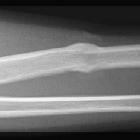

Greenstick

fracture • Greenstick fracture with callus formation - Ganzer Fall bei Radiopaedia